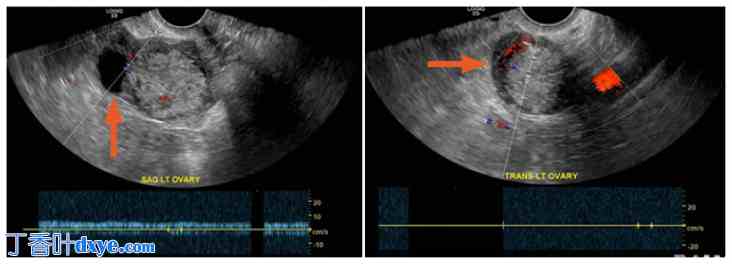

腹部 CT 扫描 (CT) 显示肺底清晰。肝脏、脾脏、肾上腺和胰腺未见异常。未见可疑肾脏肿块或肾积水。腹部未见游离液体或淋巴结肿大,未发现游离气体。小肠未见异常,无机械性梗阻证据。未见阑尾。结肠未见异常,无壁增厚或其他异常证据。未见积气或门静脉积气。盆腔CT扫描(图3)显示膀胱、直肠及直肠周围软组织未见异常。然而,左侧附件小囊肿可能是生理性的。未见明显的游离盆腔液体或淋巴结肿大。未发现急性骨性病变。双侧L5椎体部缺损,L5相对于S1呈2度前移。患者未发现盆腔内急性病变。

盆腔 CT 无造影未见异常。